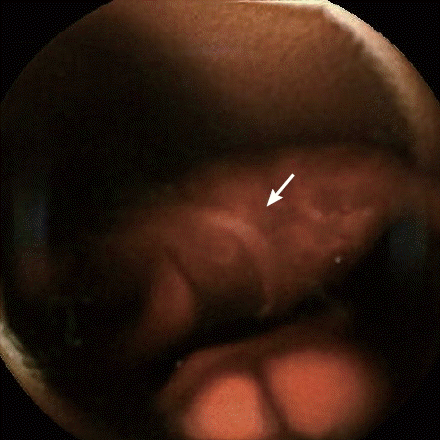

Fig. 2). A capsule endoscopy demonstrated fresh blood in the jejunum and multiple worm-like objects in the jejunum and ileum, all with a similar curvature and large “heads” (

Figs. 3,

4). The images were concerning for a hookworm infection.

Fig. 3Capsule endoscopy identified hookworms in the patient’s intestine.

Fig. 4Another capsule endoscopy identified a hookworm (arrow) in the patient’s intestine.